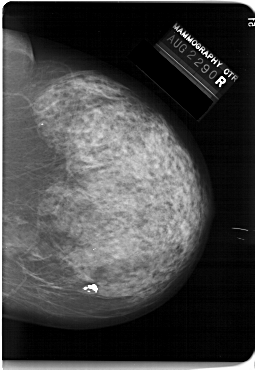

A_1146_1.RIGHT_CC

RIGHT_CC LINES 6646 PIXELS_PER_LINE 4576 BITS_PER_PIXEL 12 RESOLUTION 43.5 NON_OVERLAY